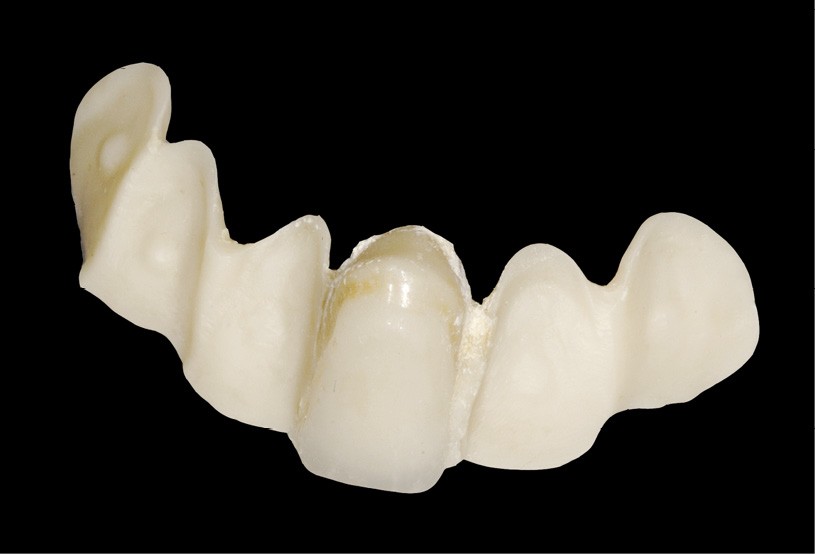

À l‘époque de la réalisation de l’attelle, le choix du matériau se faisait entre le métal et la zircone. Les inconvénients majeurs de ces deux matériaux résident dans la complexité du protocole de collage [3] d’une part, et dans le manque de fiabilité à long terme de ce dernier, d’autre part (fig. 4).

S’ajoutent à cela des difficultés de repositionnement en cas d’échec du collage initial.